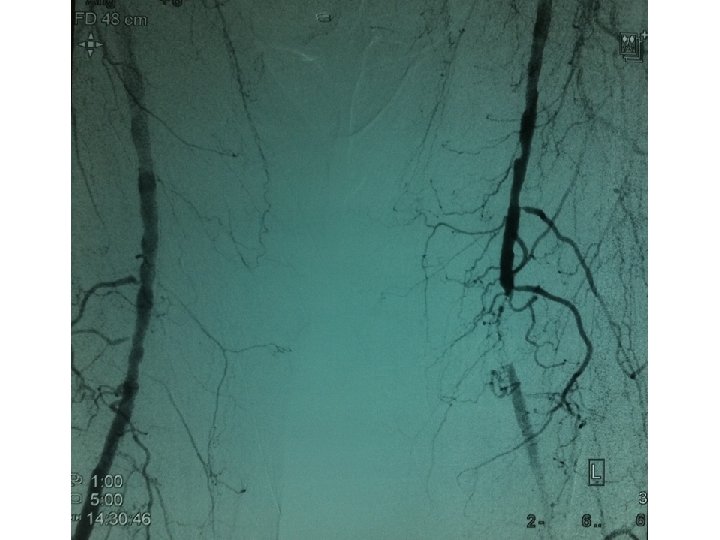

ΕΠΙΛΟΓΗ STENT Carotid angioplasty and stenting

ΕΠΙΛΟΓΗ STENT • • Carotid (self-expandable, braided or nitinol) Vertebral (balloon expandable) Subclavian (balloon expandable) Inominate (balloon expandable) Renal (balloon expandable) Aorta (nitinol, balloon expandable) Common Iliac (balloon expandable, nitinol) Ext. Iliac (nitinol)

ΕΠΙΛΟΓΗ STENT • • • Internal Iliac (balloon expandable) Common Femoral (nitinol) Deep Femoral (balloon expandable) SFA (nitinol, PTA only) Popliteal (sheet, coil nitinol, PTA only) Infrapopliteal (unknown)